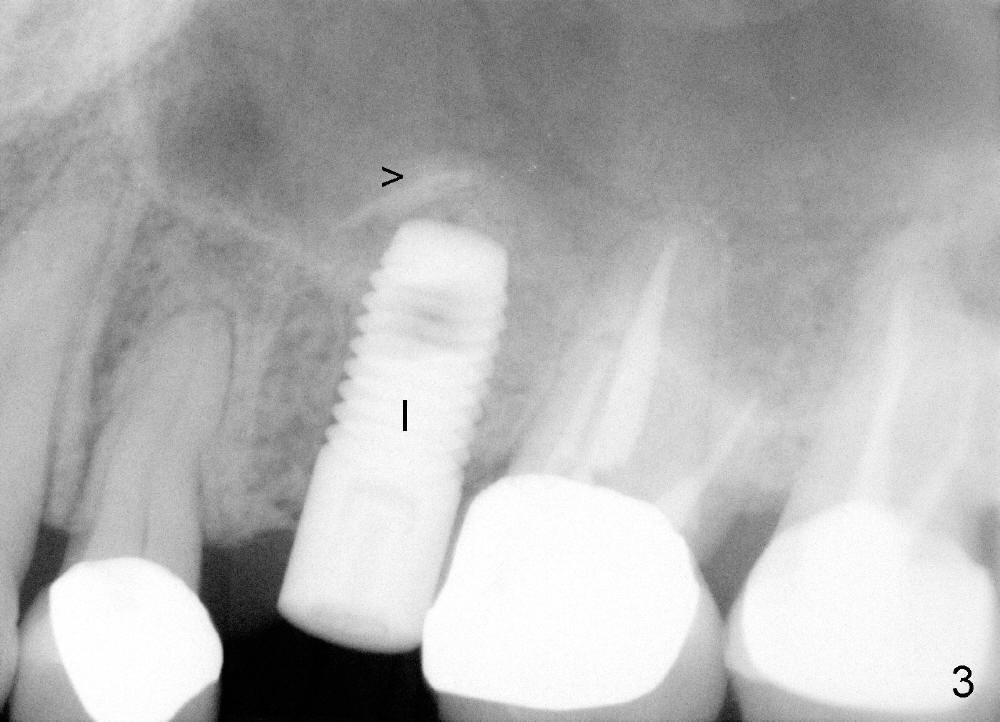

A 59-year-old lady used to have a 3-unit bridge in the upper left quadrant. A 4.5x6mm Bicon implant (Fig.1 B without extruding into the sinus) was placed in the atrophic pontic area 5 months earlier. When the abutment (A) was removed, the implant came out. The osteotomy was processed with a 4.5x14 mm tapered tap, which was unstable. When a 4.8 mm cylindrical tap was placed (past the sinus floor), it was tight (Fig.2). A 5x14 mm cylindrical implant (Fig.3 I) was inserted with elevation of the apparent sinus floor (>, no allograft used in case of sinus infection). Seven months postop, the density of sinus floor increases (Fig.4 <). The implant is stable and processed for crown (Fig.5 C, different view of the lifted sinus floor (<)). While sinus floor density is decreasing, the mesial and distal bone density is increasing 6 months (Fig.6), 1 year 6 months (Fig.7) and 3 year 6 months (Fig.8) post cementation.